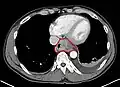

Contrast CT scan showing an esophageal tumor (axial view)

Additional testing is needed to assess how much the cancer has spread (see § Staging, below). Computed tomography (CT) of the chest, abdomen and pelvis can evaluate whether the cancer has spread to adjacent tissues or distant organs (especially liver and lymph nodes). The sensitivity of a CT scan is limited by its ability to detect masses (e.g. enlarged lymph nodes or involved organs) generally larger than 1 cm.[43][44] Positron emission tomography is also used to estimate the extent of the disease and is regarded as more precise than CT alone.[45] PET/MR as a novel modality has shown promising results in preoperative staging with fair feasibility and good correlation in comparison to PET/CT. It can enhance tissue differentiation with lowering the radiation dose to the patient.[46] Esophageal endoscopic ultrasound can provide staging information regarding the level of tumor invasion, and possible spread to regional lymph nodes.